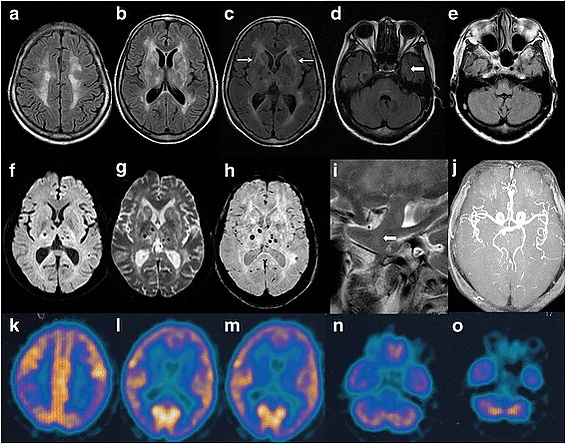

Это приводит к накоплению амилоидных бляшек в таламусе, отделе мозга, отвечающем за сон. Амилоидные бляшки постепенно уничтожают таламус и вызывают бессонницу, осложнения и летальный исход спустя несколько месяцев[9][10].